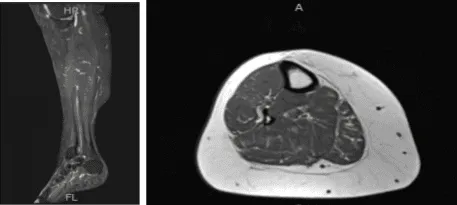

MRI- Right Calf Non-contrast

The patient is here for a follow up with an MRI of the right calf to review. Results showed no evidence of tibial stress fracture or stress reaction. Calf musculature is normal.

Degenerative changes within the knee as well as a small popliteal cyst are better appreciated on the recent knee MRI. Limited evaluation of the ankle demonstrates chronic plantar fasciitis and a partial tear at the origin of the central cord.